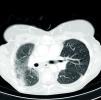

A TAC torácica de alta resolução com contraste (Figura 3) mostrou marcada colateralidade venosa, aspeto que se deve à interrupção da veia cava superior por obstrução, associando‐se a marcada fibrose pulmonar apical à direita e desvio do mediastino para o mesmo lado. Apresentava mínimo espaço entre a face posterior do esterno e as estruturas vasculares, nomeadamente ao nível da emergência dos troncos supra‐aórticos onde não excedia os 3mm, estando em contacto a nível da janela aorto‐pulmonar e ao nível da parede livre do ventrículo direito. A região subxifoideia apresentava‐se em contacto com a face anterior do lobo esquerdo hepático.